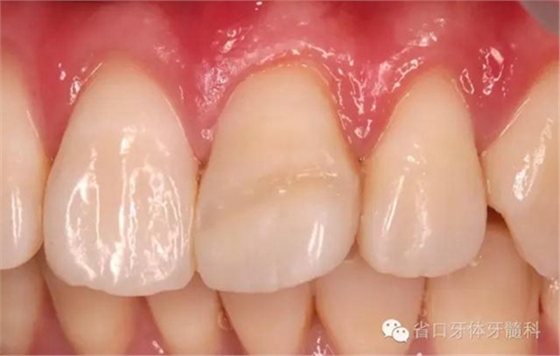

術(shù)前口內(nèi)照

口內(nèi)檢查:21切1/3-1/2折斷,髓腔暴露,探痛明顯

近中鄰面探及齲損,松-,叩+,齦緣輕度紅腫,探及齦下結(jié)石。